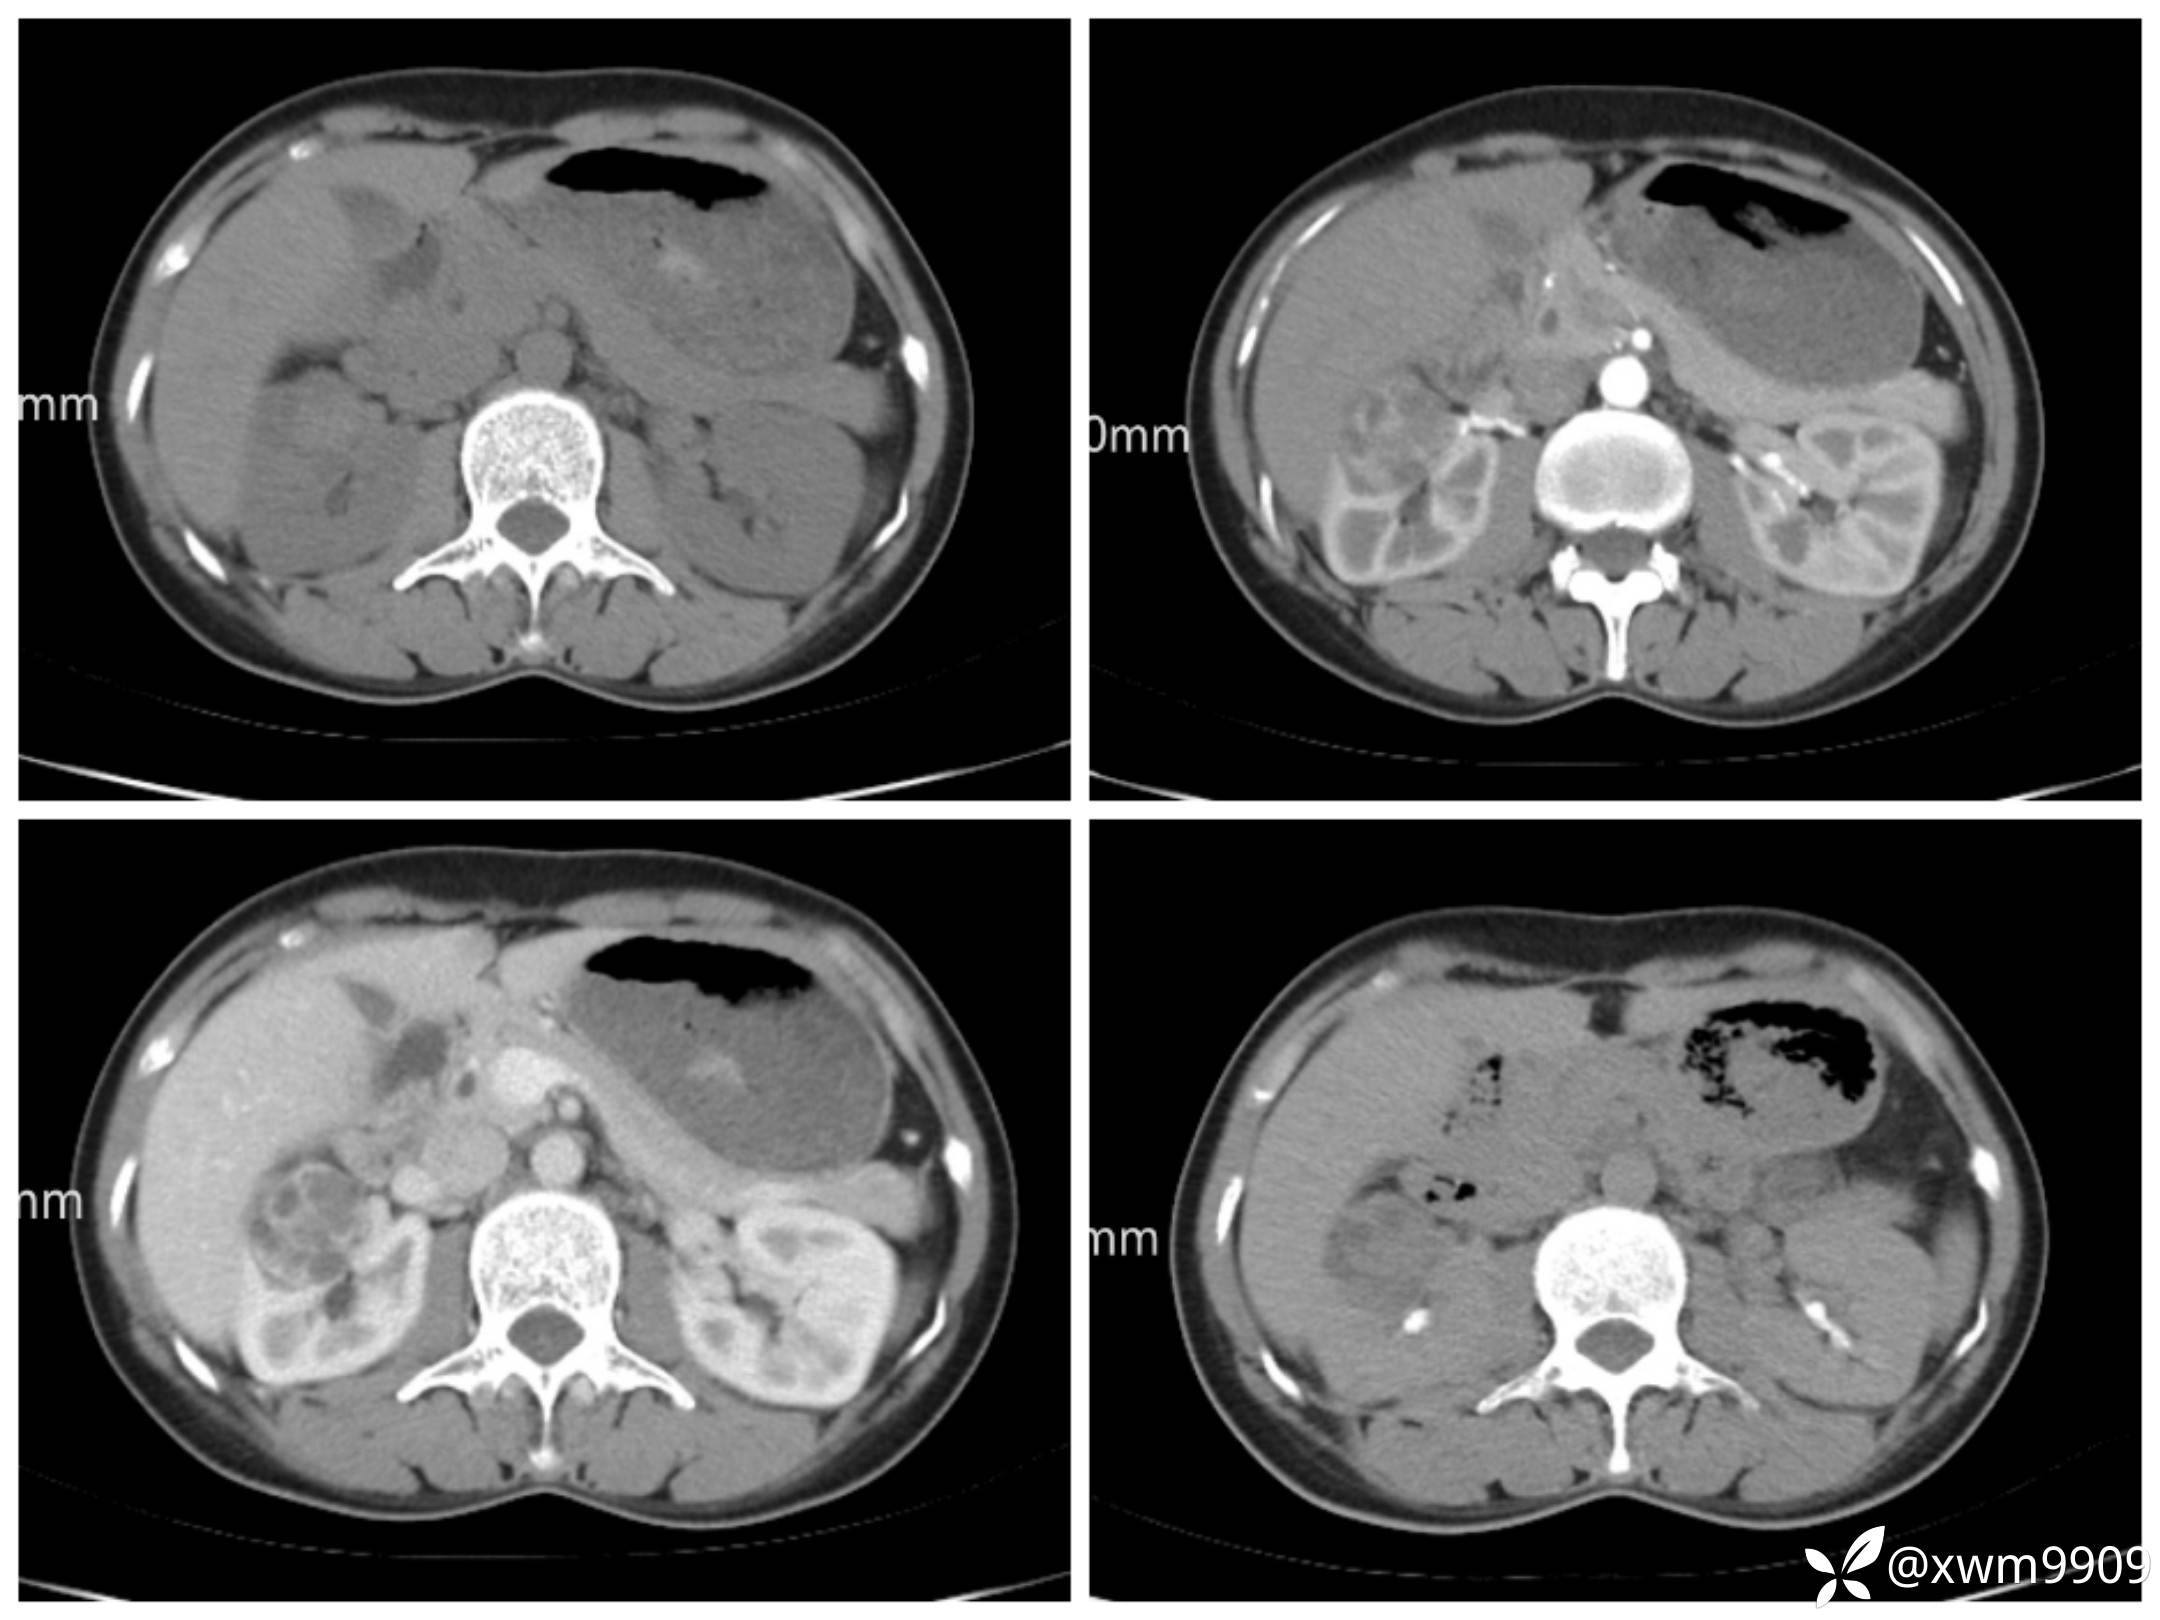

T2:

反相位:

同相位:

LAvA:

A:

v:

平衡期:

DwI丶ADC: